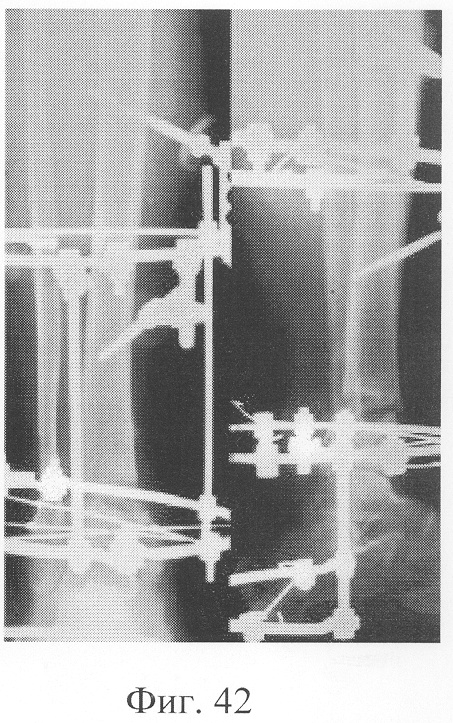

Больной Р., 46 лет, поступил для планового оперативного лечения с диагнозом «ложный сустав правой большеберцовой кости с варусно-антекурвационной деформацией» (фиг.34-37 клинико-рентгенологические данные до операции). Предшествующее лечение перелома проводилось консервативным способом, можно отметить несостоятельность и недостаточную продолжительность иммобилизации, что является у данного пациента основным фактором в формировании ложного сустава. Из сопутствующей патологии необходимо отметить гипертоническую болезнь II ст., ИБС, атеросклеротический кардиосклероз, НК II А ст. Во время операции произведена экономная резекция фрагментов, устранение деформации в аппарате внешней фиксации, костная пластика деминерализованным костным трансплантатом, заселенным аутологичными мезенхимальными стволовыми клетками, по предложенной методике (при этом костный паз был выполнен по внутренней поверхности в области диастаза между костными фрагментами). В послеоперационном периоде дренажи удалены на 2-е сутки, швы сняты на 21 сутки в связи с развитием краевого некроза в области послеоперационной раны. Ходьба при помощи костылей с 7-х суток послеоперационного периода, дозированная нагрузка на конечность с третьего месяца после операции с учетом локализации повреждения в дистальной части большеберцовой кости (фиг.38-42 – клинические и рентгенологические данные в процессе лечения). Из осложнений необходимо отметить воспаление в области чрескостных элементов в конце периода фиксации, что купировано после снятия аппарата. Демонтаж аппарата внешней фиксации через 5,5 месяцев при клинико-рентгенологической картине сращения.